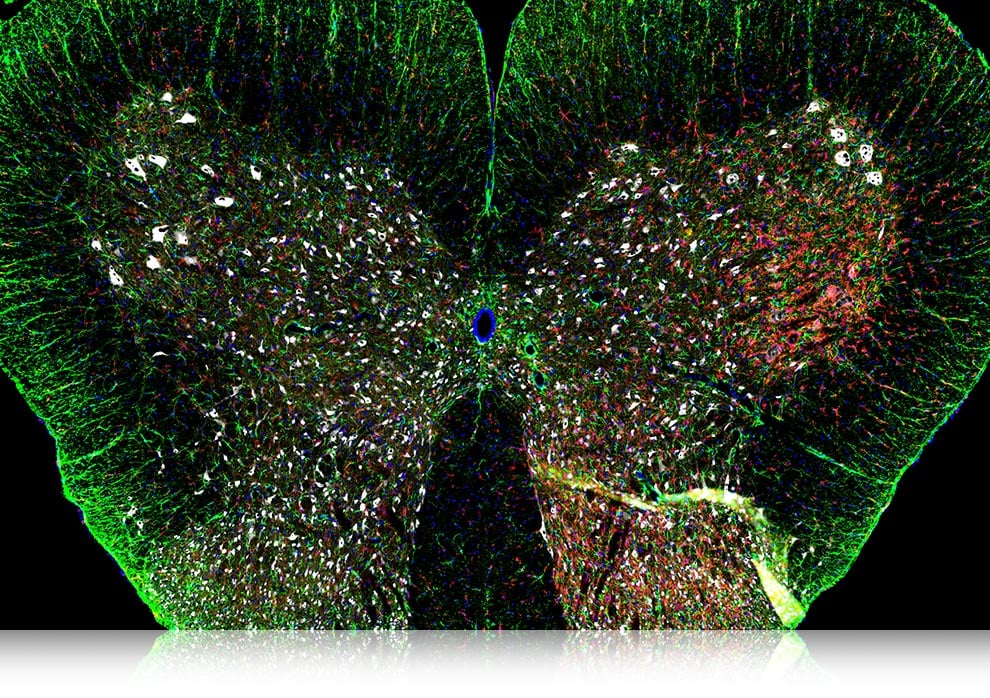

細部まですべてにラットの脊髄

ご提供/愛媛大学大学院医学系研究科 麻酔・周術期学教室 西原佑 講師